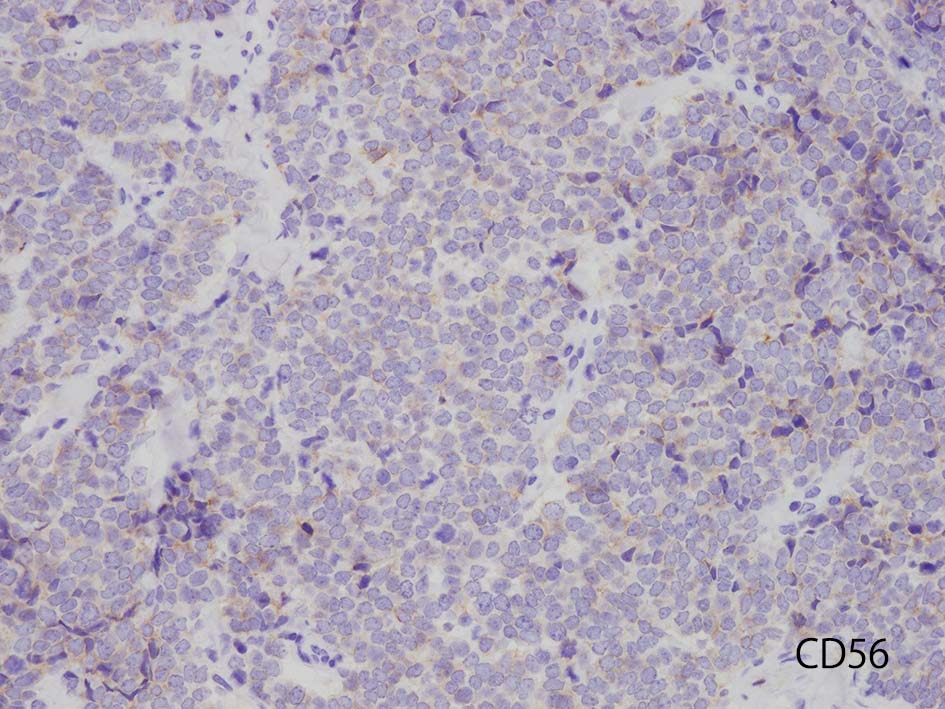

CD56

本例ではCD56は淡くそまるのみであった. 浜松医大病院病理で染色していただいた, MCpvVは核に陽性となっている.